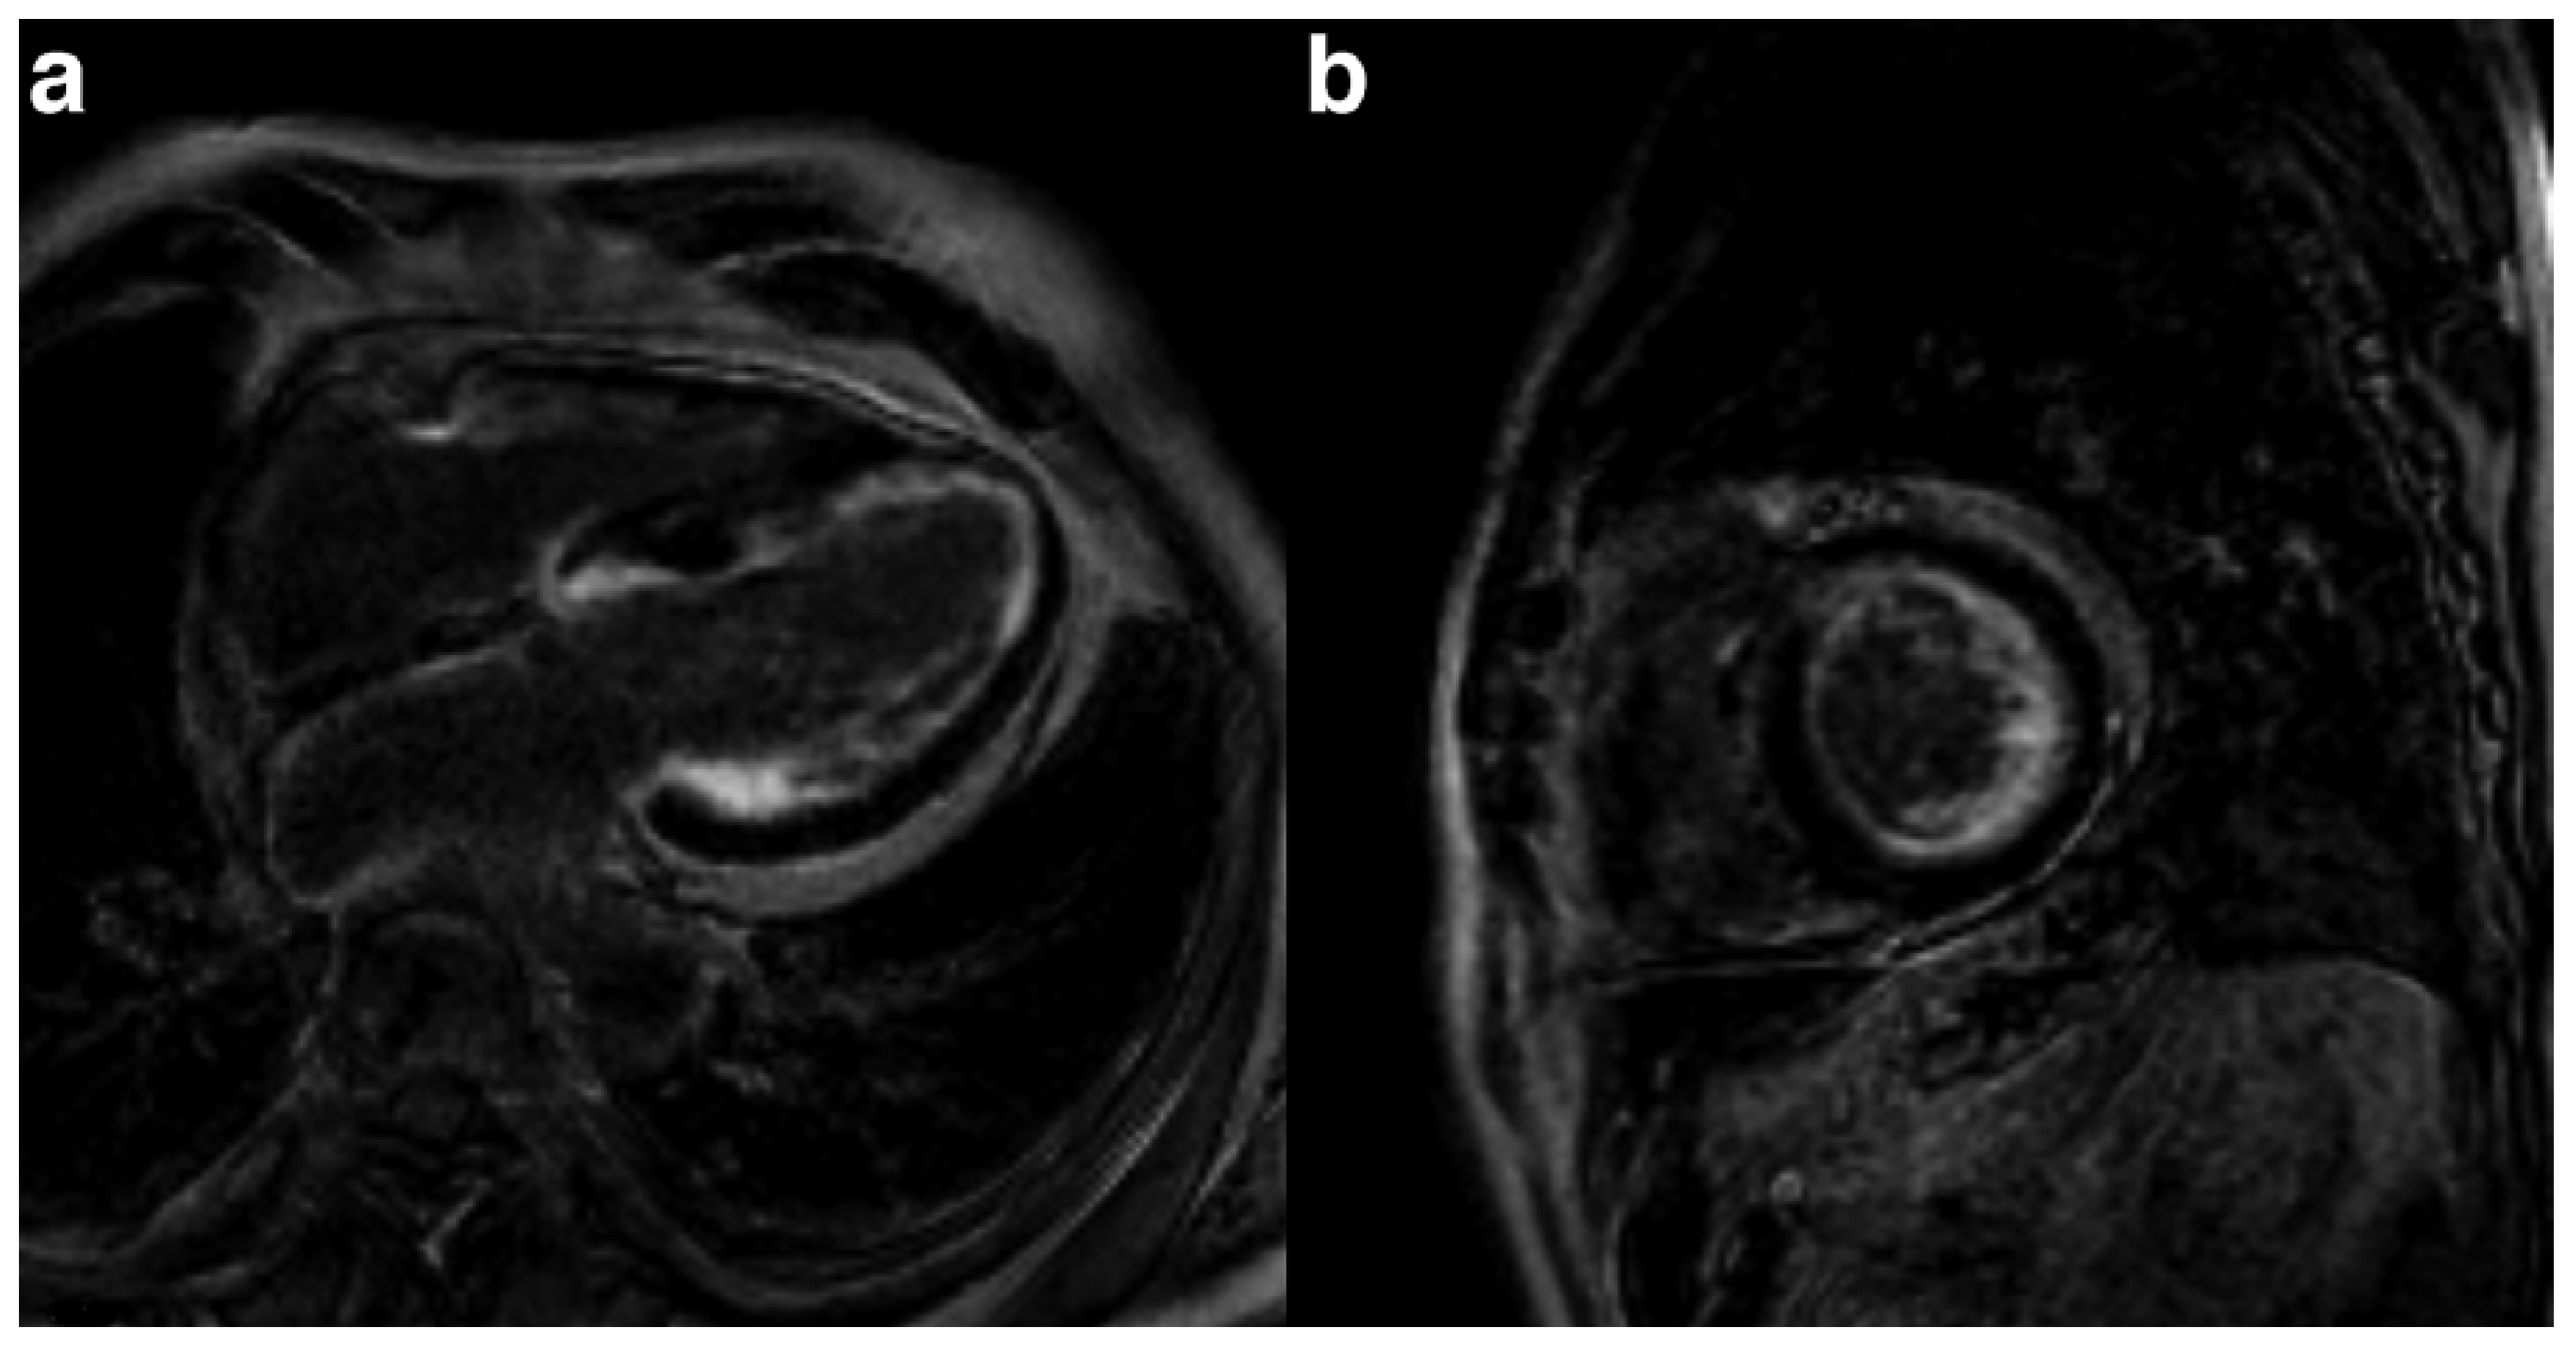

How do we diagnose cardiac amyloidosis?